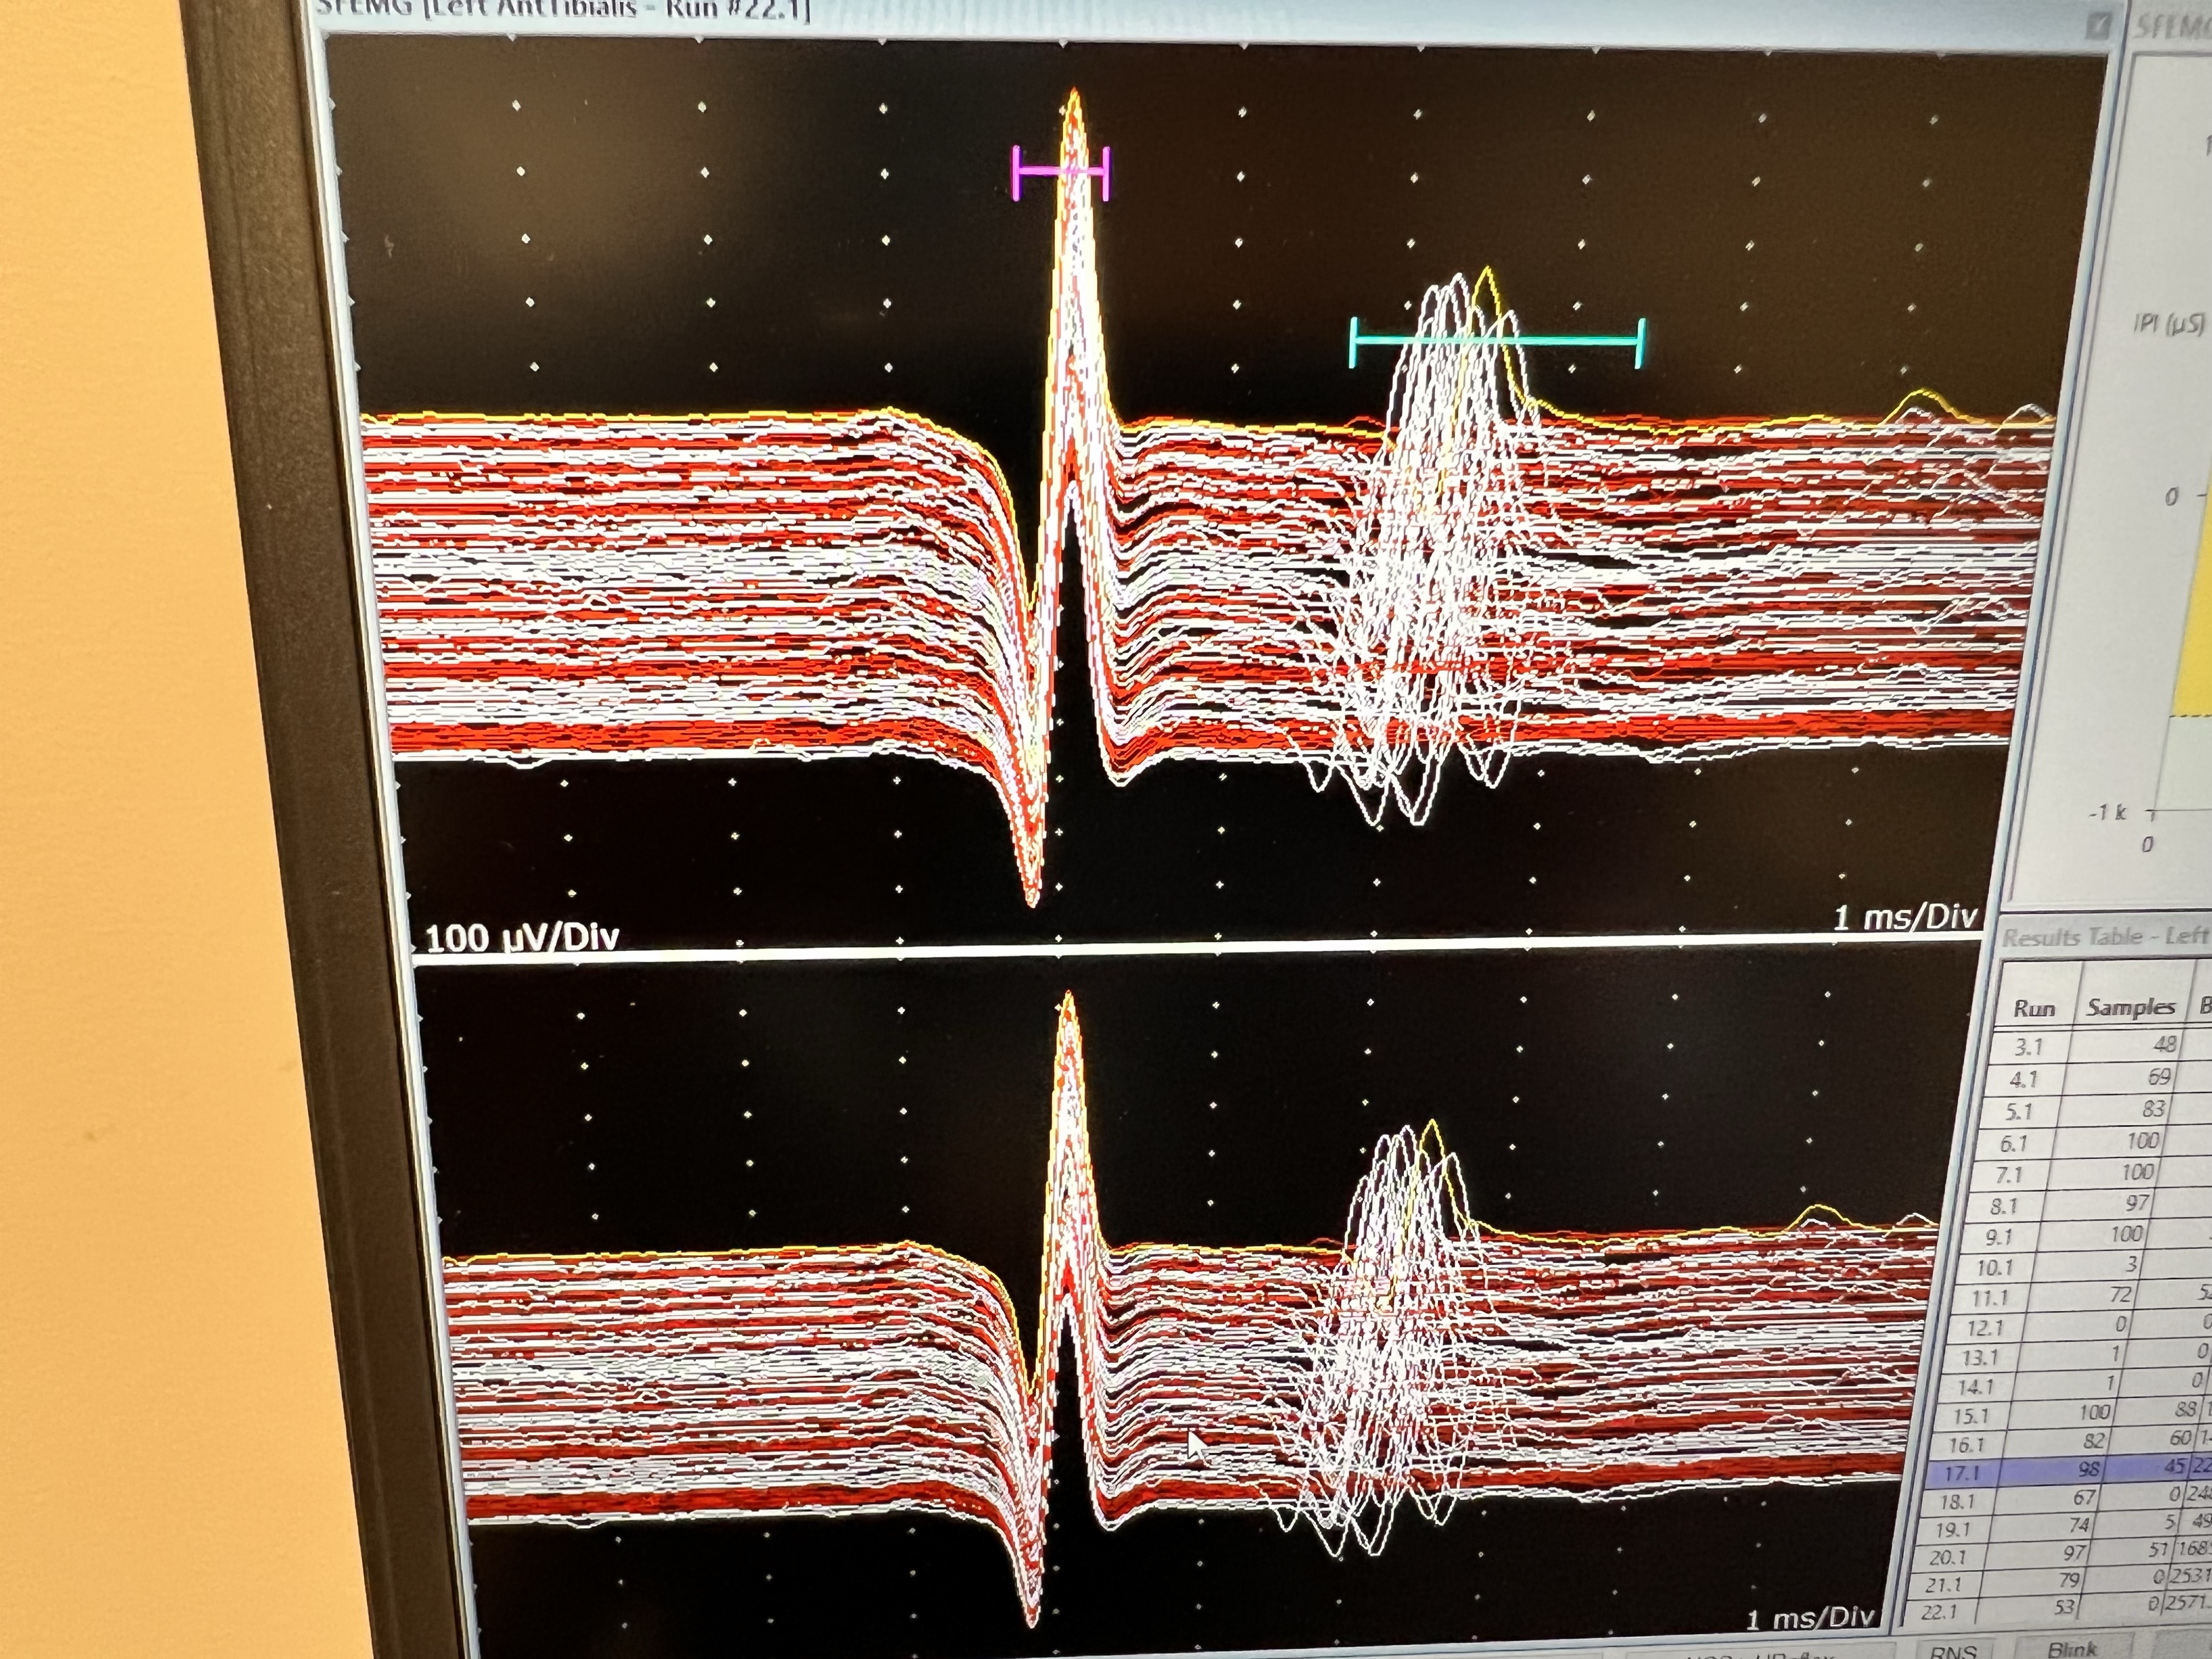

Single Fiber Electromyography

Voluntary SFEMG